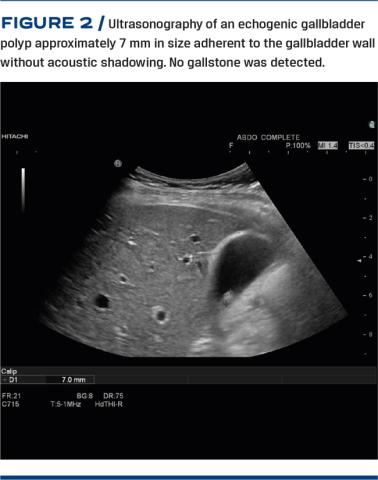

All technical parameters such as gain and focus were adjusted individually. Polyps were identified if the lesion was immobile without acoustic shadowing. Its largest diameter was measured in mm using an electronic ruler. An increase of polyp size of 2 mm was considered a significant growth. If potential gallstones were detected, this was documented by the presence or absence of acoustic shadowing. A picture archive communication system was used to store all imaging and ultrasonography reports. Figure 2 shows ultrasonography of an echogenic gallbladder polyp approximately 7 mm in size without acoustic shadowing.